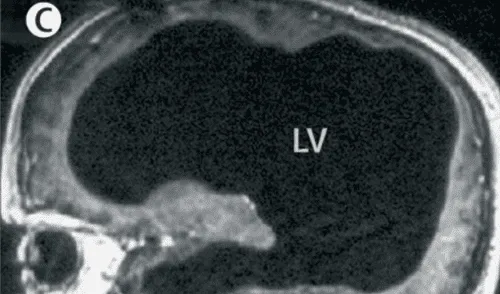

Tras una tomografía cerebral, los médicos descubrieron que su cerebro ocupaba apenas un 10 % del espacio craneal. El resto estaba invadido por líquido cefalorraquídeo. A pesar de esta condición, el paciente llevaba una vida completamente funcional: tenía un empleo estable, estaba casado y era padre de dos hijos.

Sin embargo, el tratamiento no detuvo el avance del trastorno. Con el paso de las décadas, el líquido volvió a acumularse de forma crónica y silenciosa, reduciendo progresivamente el volumen del cerebro. En 2003, una nueva evaluación por imágenes reveló que la masa cerebral se había comprimido hasta convertirse en una delgada capa adherida al cráneo.

Los estudios mostraron una dilatación extrema de los ventrículos cerebrales, un adelgazamiento de la corteza y la aparición de un quiste en la fosa superior. Los neurólogos del Hospital de la Universidad Mediterránea de Marsella, liderados por el doctor Lionel Feuillet, diagnosticaron hidrocefalia no comunicante, probablemente originada por una obstrucción en el foramen de Magendie, una apertura crucial para la circulación del líquido cefalorraquídeo.